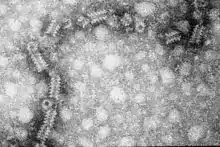

Electron micrograph of the ribonucleoprotein of mumps virus, which has a herring-bone like structure